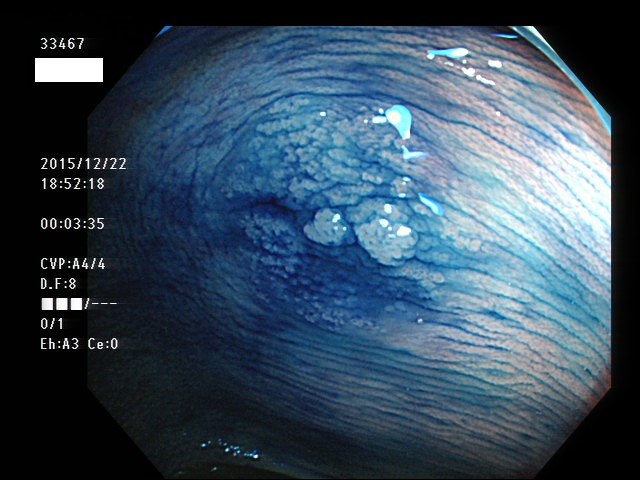

上記100名より抽出した平坦・陥凹型腺腫(=癌化の危険が高いが見落としやすい病変)の内視鏡写真